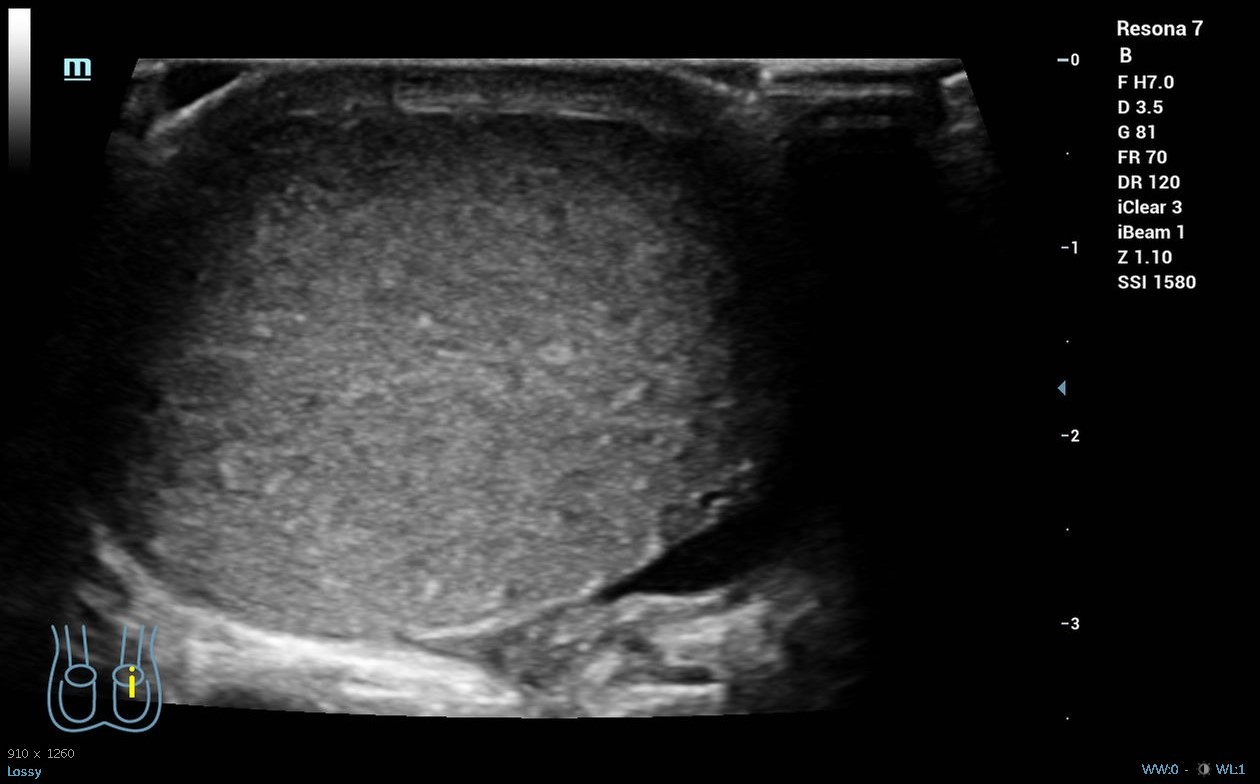

Hombre de 19 años sin antecedentes de interés que acude a la guardia del centro de salud por dolor súbito en el testículo derecho desde las 04.00 h que le ha despertado, asociado a náuseas y vómitos, sin otra clínica infecciosa o traumática acompañante. A la exploración física presenta abdomen normal, pero teste izquierdo ascendido y horizontalizado, doloroso a la palpación, con discreto aumento de tamaño o cambios en temperatura, con signo de Prehn negativo y reflejo cremastérico ausente en lado izquierdo. Se realiza ecografía clínica, donde se objetiva testículo izquierdo aumentado de tamaño con morfología y ecoestructura normal, pero con ausencia de flujo power-Doppler en su interior, ligero hidrocele y aparente giro del cordón espermático en su porción distal.

Derivación hospitalaria urgente, donde se corroboran los hallazgos de la ecografía clínica y se realiza detorsión quirúrgica.